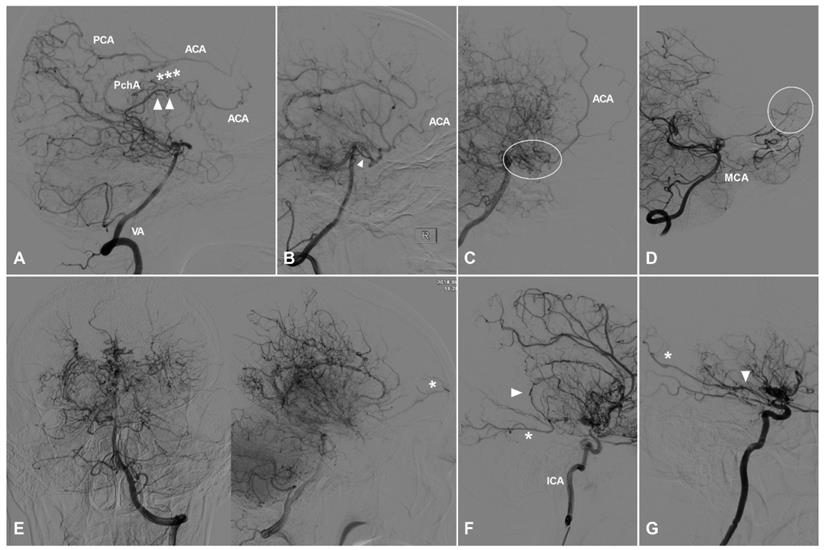

TDCs through the AEA

TDCs through the AEA can be divided into 3 types. Type Ⅰ: The AEA courses anteriorly and continues as the anterior falx artery (AFA). The AFA courses superiorly and posteriorly and anastomoses with the cortical arteries of the frontal lobe [9]. Type Ⅱ: The AEA courses superiorly and anastomoses directly with the cortical arteries of the frontal lobe. Type Ⅲ: The AEA gives rise to multiple branches coursing anteriorly and superiorly and anastomoses with the cortical arteries of the frontal lobe. TDCs from the AEA are illustrated in Figure 1.

Figure 1

TDCs through the anterior ethmoid artery. A, Angiogram of the ICA (left) in lateral view shows the AEA courses anteriorly after originating from the OphA, then turns superiorly and anastomoses with the AFA and the cortical artery of the frontal lobe (type I). The same angiogram (right) in late arterial phase shows the frontal lobe (oval) is well vascularized by collaterals. B, Angiogram of the ICA (left) in lateral view shows the AEA (asterisk) courses superiorly after originating from the OphA and anastomoses directly with the cortical artery (arrow head) of the frontal lobe (type II). The same angiogram (right) in late arterial phase shows the frontal lobe (oval) is poorly vascularized by collaterals. C, Angiogram of the ICA (left) in lateral view shows the AEA courses superiorly (asterisk) and anteriorly and anastomoses with the cortical artery and AFA (arrow head) (type III). Angiogram of the ECA (right) in the same patient shows MMA also participates in the TDCs through the AEA (asterisk and arrow head). D, Angiogram of the ECA shows the IMA (oval) also participates in the TDCs through the AEA (asterisk). E, Angiogram of the ECA shows the FA (oval) also participates in the TDCs through the AEA (asterisk). Abbreviations: AEA, anterior ethmoid artery; AFA, anterior falx artery; ECA, external carotid artery; FA, facial artery; ICA, internal carotid artery; IMA, internal maxillary artery; MMA, middle meningeal artery; OphA, ophthalmic artery; TDC, transdural collateral.

TDCs through the PEA

TDCs through the PEA can also be divided into 3 types. Type Ⅰ: The PEA courses posteriorly and only anastomoses with the orbitofrontal artery at the frontal base. Type Ⅱ: The PEA courses posteriorly and anastomoses with the other big branches of the anterior cerebral artery (ACA). Type Ⅲ: The PEA courses posteriorly and anastomoses with the main trunk of ACA. TDCs from the PEA are illustrated in Figure 2.

Figure 2

TDCs through the posterior ethmoid artery. A, Angiogram of the ICA in lateral view shows the PEA (asterisks) courses posteriorly after originating from the OphA and anastomoses with the orbitofrontal artery at the frontal base (type I). B, Angiogram of the ICA in lateral view shows the PEA (asterisks) courses posteriorly after originating from the OphA and anastomoses with the branches of the ACA (type II). C, Angiogram of the ICA in lateral (left) and AP (right) views shows the PEA (asterisks) courses posteriorly after originating from the OphA and anastomoses with the main trunk (arrow head) of the ACA (type III). D, Angiogram of the ECA shows the IMA also participates in the TDC of PEA (asterisks). E, Angiogram of the ECA shows the MMA also participates in the TDC of PEA (asterisks). Abbreviations: ACA, anterior cerebral artery; AP, anteroposterior; ECA, external carotid artery; ICA, internal carotid artery; IMA, internal maxillary artery; MMA, middle meningeal artery; OphA, ophthalmic artery; TDC, transdural collateral.